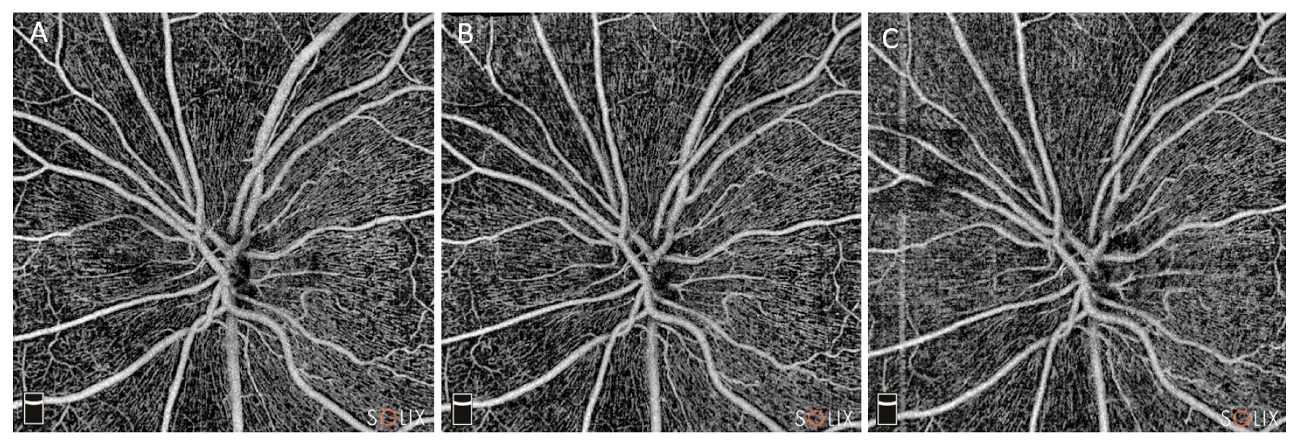

The analysis of optic nerve head microvascular parameters showed a significant increase in the whole image vessel density at T7 compared to the preoperative period (from 49.6 ± 2.7 to 51.4 ± 4.6%, p = 0.001), but returned to preoperative values at T30 (49.3 ± 4.0%, p = 0.95). Similarly, RCP vessel density showed a transient increase at T7 when compared to T0 (48.5 ± 6.2 vs. 45.6 ± 4.2%, p = 0.001), but no significant changes were reported at T30 when compared to baseline values (44.8 ± 4.6 vs. 45.6 ± 4.2%, p = 0.24) (Figure 2).

Figure 2. AngioVue Disc image of optic nerve head microvascularization during the follow ups: baseline (A), one week after cataract surgery (B) and one month after surgery (C). At last follow up, peripapillary vascular density is substantially unchanged when compared to baseline.